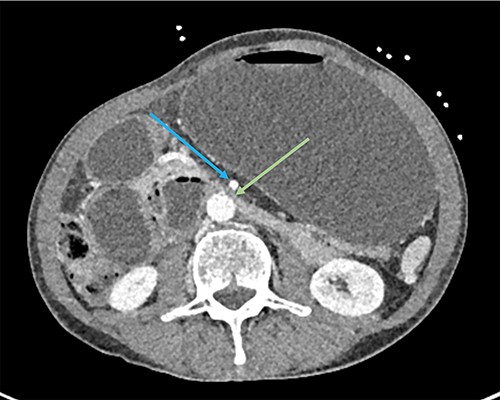

A 73-year-old male was transferred from a private hospital to the local public hospital 5 days post left total hip replacement with a 2-day history of nausea, bilious vomiting and colicky abdominal pain. His bowels had not opened since prior to the procedure. His background included previous right total hip replacement, benign prostate hyperplasia and depression. His medications included mirtazapine, tamsulosin, calcium carbonate and denosumab. He is a non-smoker and does not drink alcohol. On examination his observations were all within normal limits and he appeared to be very slim build. His height was 174 cm and he weighed 49 kg with a body mass index of 16.2. His abdomen was generally tender and distended, but not peritonitic. His blood results showed a serum potassium of 3.2 mmol/L, sodium 148 mmol/L, magnesium 0.94 mmol/L, albumin 34 g/L, creatinine 104 μmol/L, eGFR 61 ml/min (acute kidney injury), white cell count 7.7 × 109/L, haemoglobin 114 g/L. A computed tomography (CT) scan of his abdomen (Figs 1–3) showed a grossly distended stomach measuring 26.2 cm × 14.3 cm × 14.6 cm. It appeared fluid filled with moderate distension of the first and second part of the duodenum. The third part of the duodenum was partly fluid filled with an abrupt luminal collapse within the distal aspect where it passes between the superior mesenteric artery and aorta. The aorta mesenteric angle was reduced to ~23°. The remaining small bowel was decompressed with no free fluid or gas.

CT showing grossly distended stomach, first and second part of duodenum with sudden collapse and obstruction of duodenum (green arrow) at the superior mesenteric artery (blue arrow).